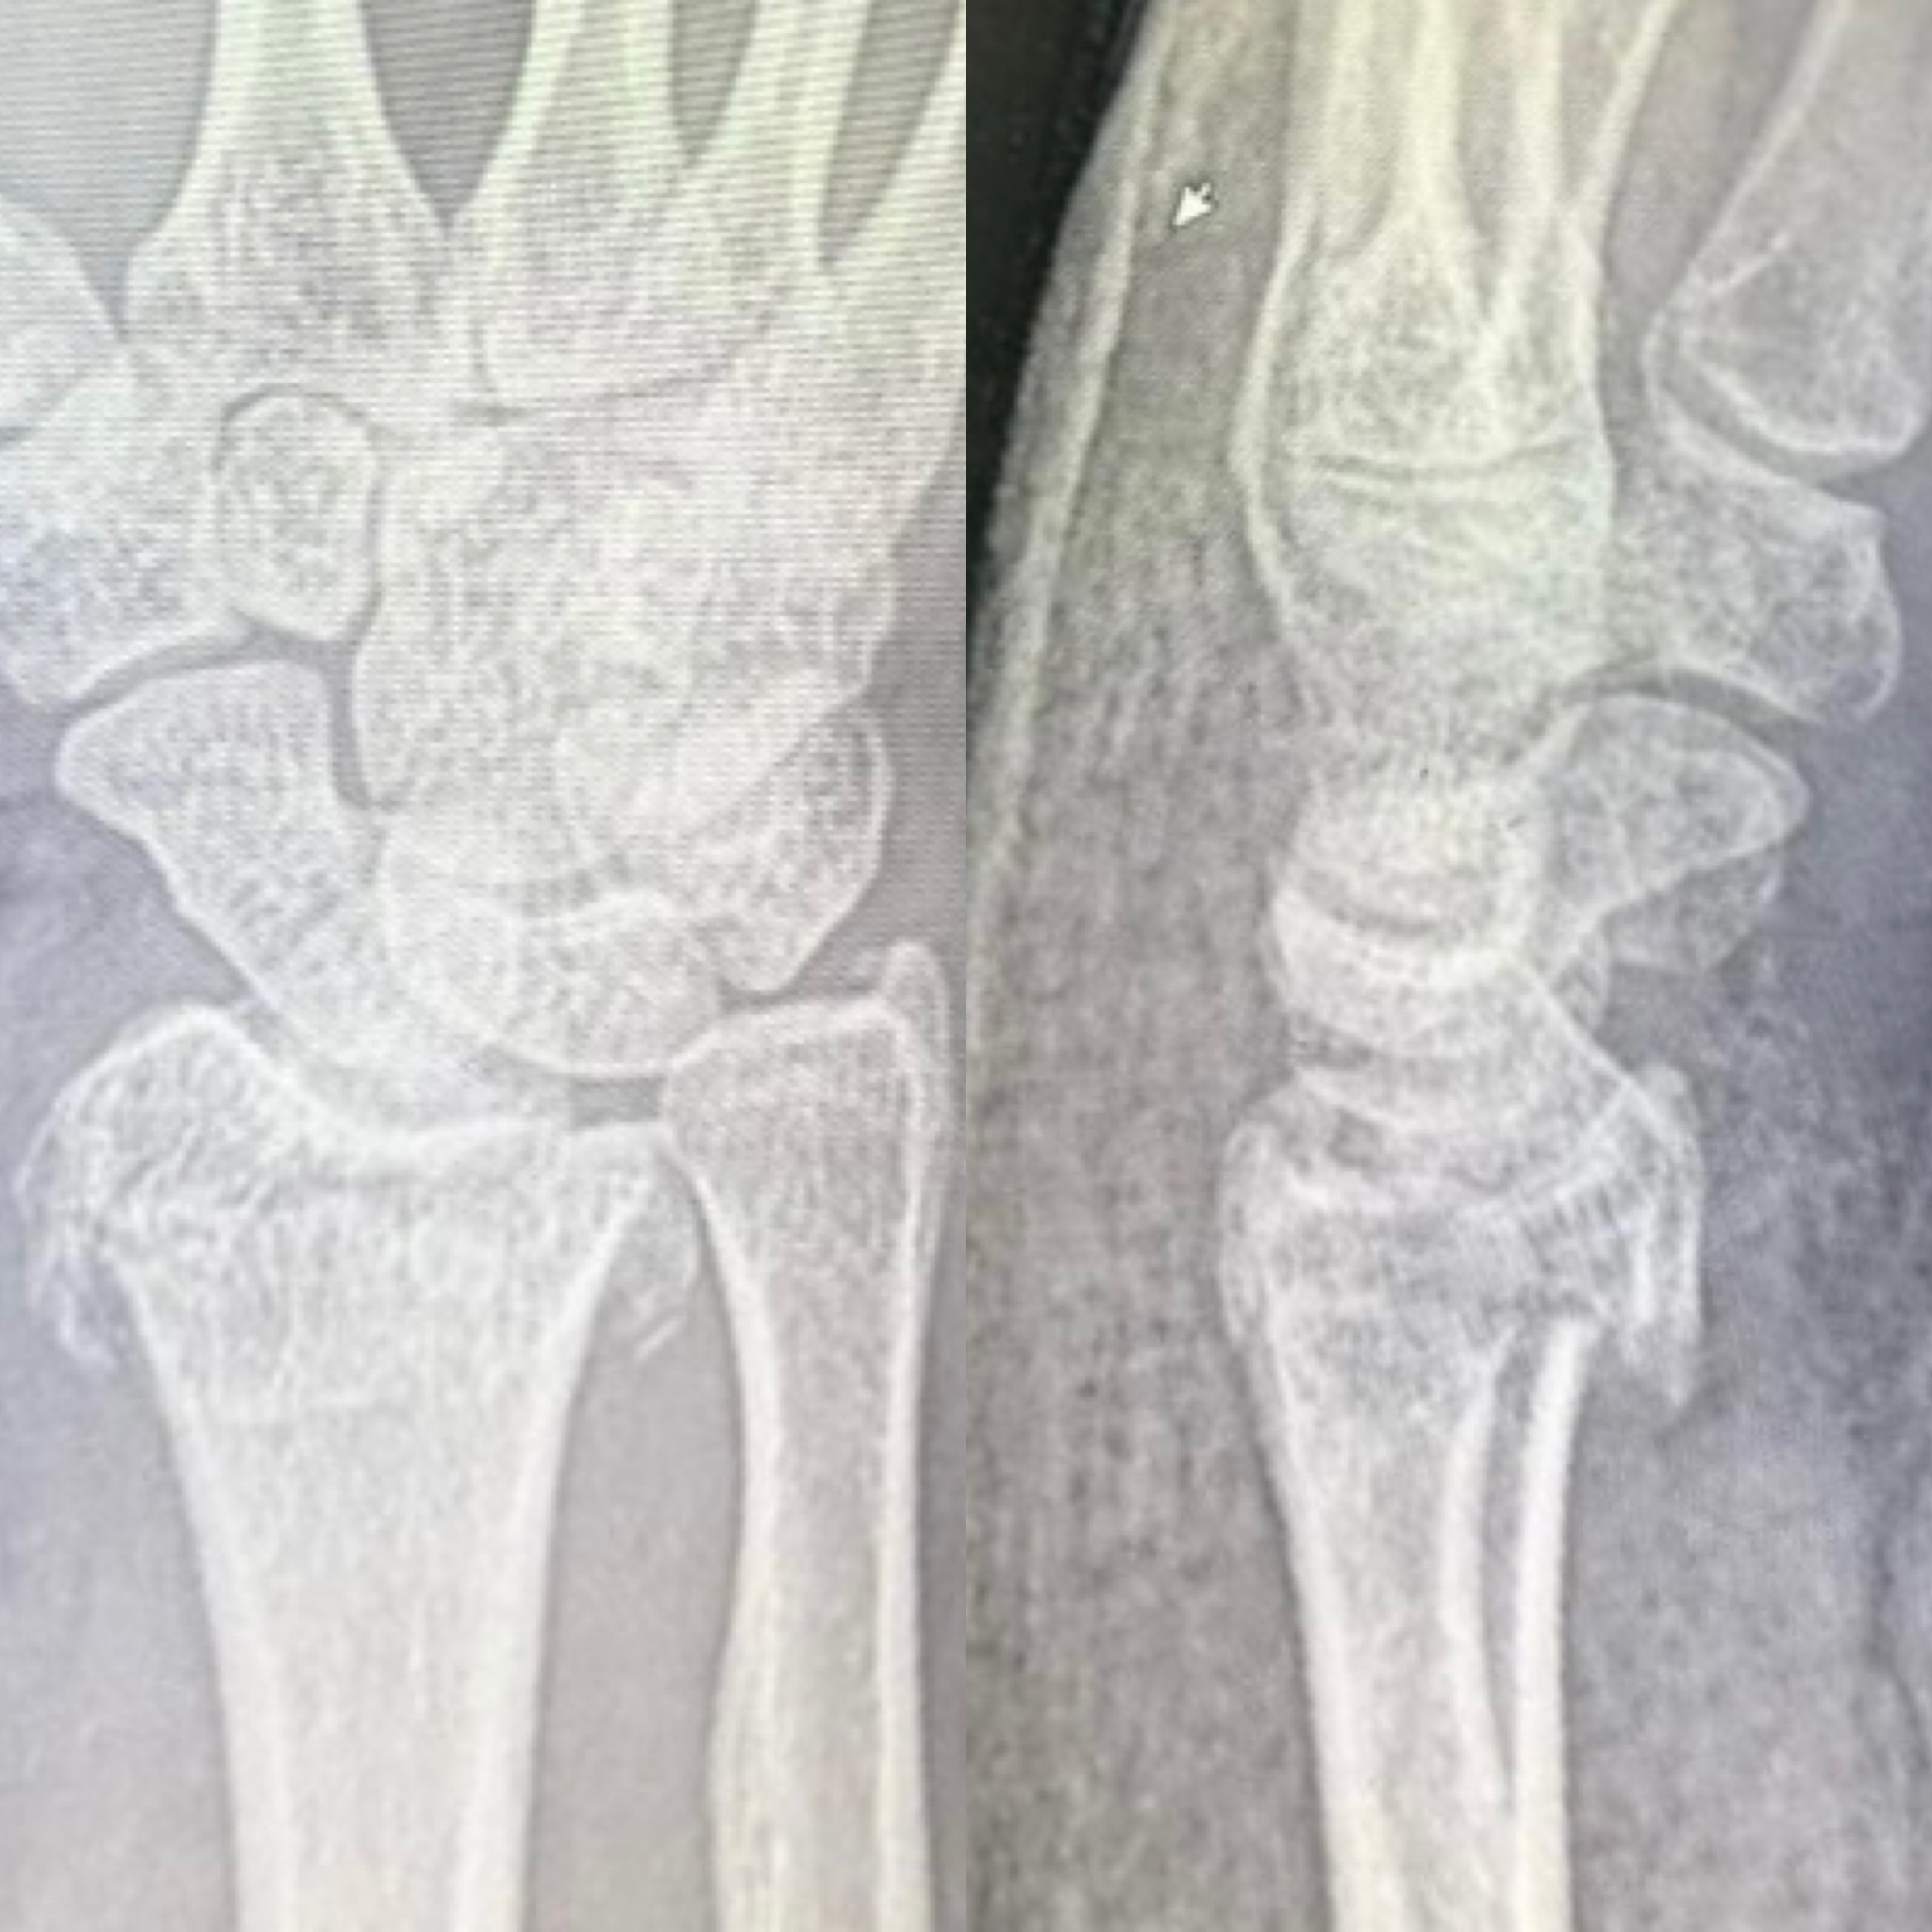

Клинический случай: внутрисуставной перелом дистального метаэпифиза лучевой кости — до операции